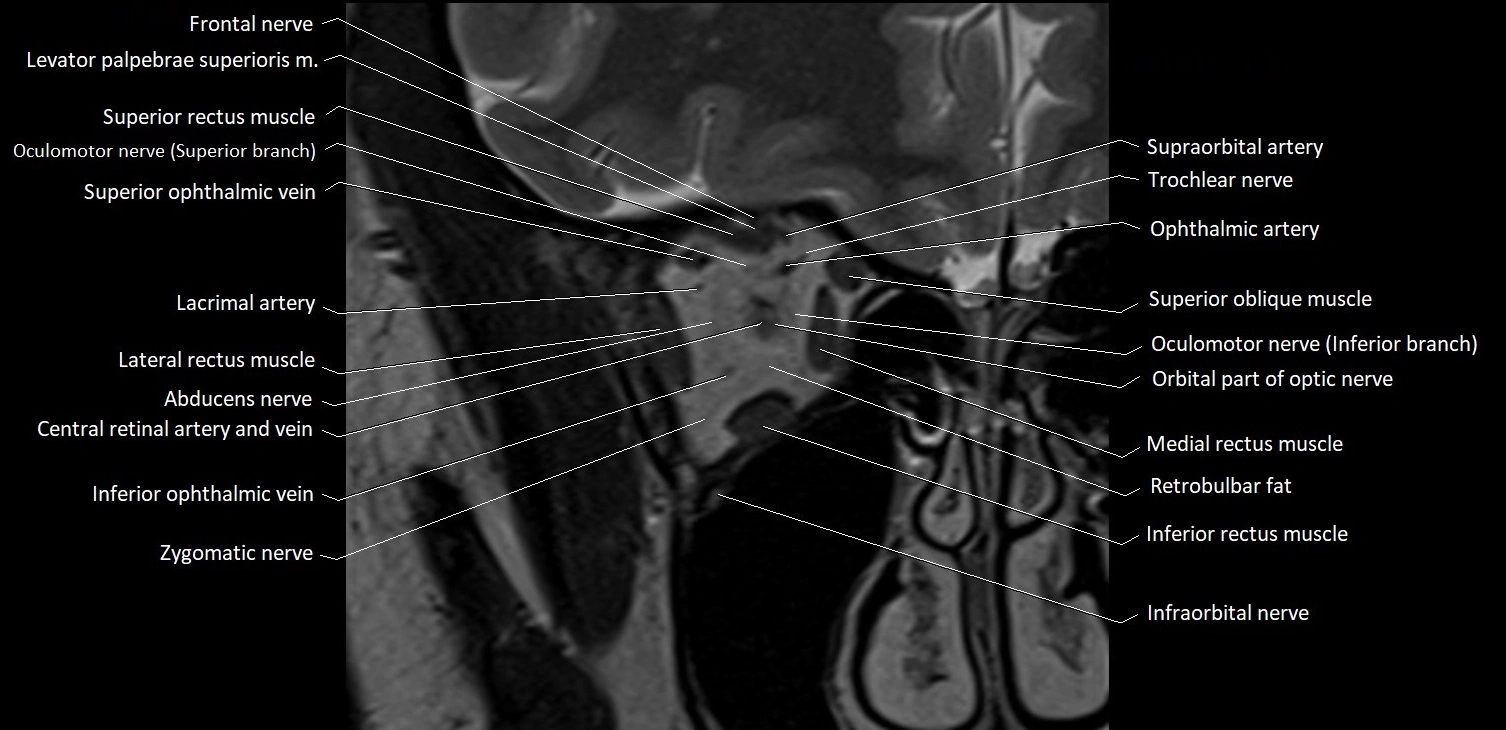

- Abducens nerve (Cranial nerve VI)

- Abducens nerve (orbital part )

- Frontal nerve

- Inferior ophthalmic vein

- Inferior rectus muscle

- Infraorbital nerve

- Lacrimal artery

- Lateral rectus muscle

- Levator palpebrae superioris muscle

- Medial rectus muscle

- Oculomotor nerve (Superior branch)

- Oculomotor nerve (inferior branch)

- Orbital part of optic nerve

- Retrobulbar fat

- Superior oblique muscle

- Superior ophthalmic vein

- Superior rectus muscle

- Supraorbital artery

- Trochlear nerve (Cranial nerve IV)

- Zygomatic nerve

MRI images